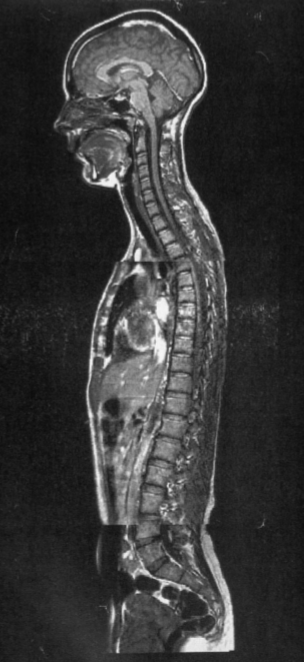

Describe the curvature of the different parts of the spine.

• Cervical -> Lordosis

• Thoracic -> Kyphosis

• Lumbar -> Lordosis

• Sacral -> Lordosis